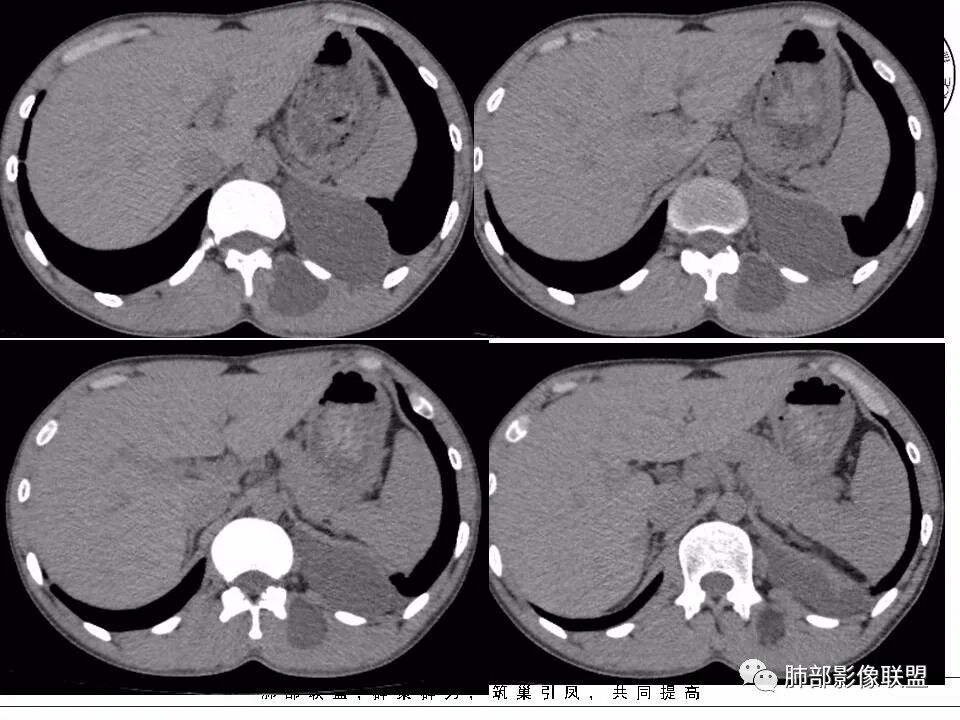

现在我们重新回顾性分析这个病例的影像特点:

1.含有少量脂肪密度成分,位于病灶中央区,应当是病灶内的一部分,或者说至少这部分不是被包绕卷入的。常见病灶内含有脂肪组织的肿瘤:多种脂肪瘤、脂肪肉瘤、畸胎瘤、其他肿瘤伴脂肪化生或分化。

2.病灶中间弧形稍高密度影,提示纤维组织可能,而且很有张力并呈分叶状,伴弧形钙化,提示这个倾向于病灶的包膜。

我们知道囊性成熟畸胎瘤中外胚层来源的上皮组织有腺体,有脂质,分泌粘液,囊性病灶有张力,囊壁也可以有弧形钙化,但易脂质上浮呈液平面,囊性畸胎瘤较少见如此明显的分叶,更少见在不同组织区间漫延串扰。

3.部位深在且四处侵入,含脂质较少或整体密度高于脂肪的脂肪类肿瘤应当想到脂肪肉瘤的可能性,因为它可以粘液样变。

但本例病灶边界清楚,有一定规模而相邻骨质未见异常,提示整体倾向良性或者恶性程度不高。

包膜钙化往往提示病灶存在时间较长且较为固定。